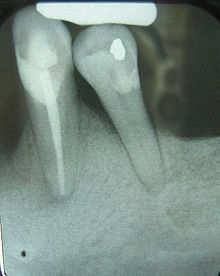

This X-ray film displays two lone-standing mandibular teeth, the lower left first premolar and canine, exhibiting severe bone loss of 30– 50%. Widening of the periodontal ligament surrounding the premolar is due to secondary occlusal trauma.